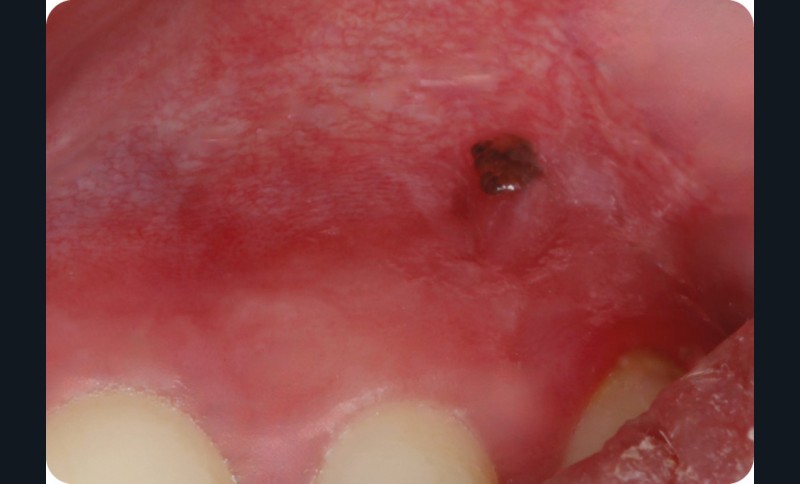

Patiente de 44 ans venue consulter sur les conseils de son dentiste traitant après la découverte, 15 jours plus tôt, d’une macule noirâtre sur la gencive.

Lors de sa dernière consultation chez son dentiste, ce dernier a découvert une macule pigmentée sur la muqueuse alvéolaire, à hauteur de 22-23. Cette lésion n’existait pas lors de la consultation précédente, un an auparavant.

La lésion était constituée par une macule noirâtre, plane, bien limitée, arrondie, de 2 mm de diamètre, siégeant sur la muqueuse alvéolaire, à la verticale de la papille interdentaire 22-23. La macule présentait un aspect tacheté associant des zones de différentes couleurs allant du noir foncé jusqu’au grisé. Il n’y avait pas d’autres lésions muqueuses, mais la patiente, bien que d’origine ibérique, présentait une peau claire avec de nombreux nævi.